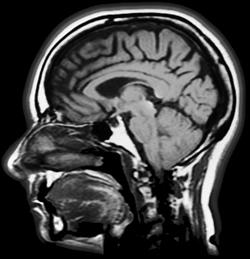

“Patients and physicians are struggling with a broken Medicare physician payment system that will result in a nearly 30 percent cut on January 1, threatening access to care for seniors. Diagnostic imaging in particular has already seen significant reductions over the past five years, with payments for some services down over 60 percent and additional cuts scheduled to occur. These proposed cuts would further threaten patients’ access to care,” Carmel said.